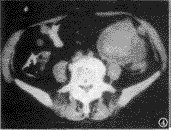

囊性转移瘤:1例,位于肝外侧缘,呈局限性椭圆形、密度均匀、无分房的囊性肿块,边缘欠清,部分囊壁呈结节状均匀强化,肝脏外缘不规则受压变形。1例为肝脏周围多个囊状占位病变,肝脏外缘受压变形(图3)。

图3 囊性转移瘤,肝脏周围多个囊状占位病变,肝脏外侧缘受压变形